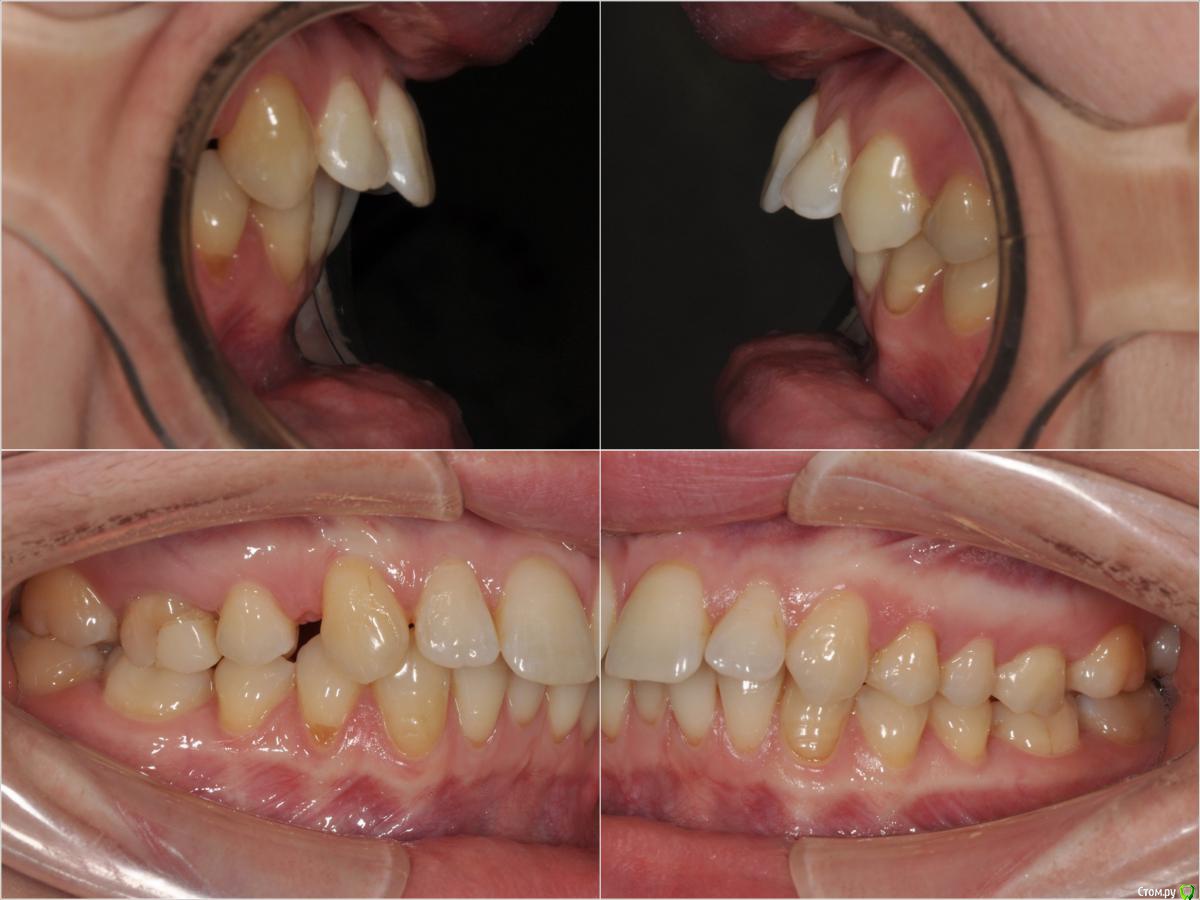

losenok83 Опубликовано 11 мая, 2016 Поделиться Опубликовано 11 мая, 2016 Здравствуйте! Мне 32 года. Год в брекетах. Уже больше 3-х месяцев беспокоит боль в в суставе, при открывании рта, иногда при жевании. До брекетов у меня хрустел сустав с левой стороны, сейчас хрустит с обеих сторон+ закладывает периодически уши. Лечусь с удалением 4-рок на ВЧ. Справа 4-ка была удалена в детстве по орт.показаниям , слева вначале нынешнего лечения. Не связана ли боль в суставе с удалением 4-рок? Действительно ли нужно было их удалять? Не нужно ли было выдвигать нижнюю челюсть вперед спец. аппаратами? И что можно сделать сейчас? Фото и снимки до лечения. Ретинированная 8-ка удалена. Ссылка на комментарий

losenok83 Опубликовано 4 сентября, 2016 Автор Поделиться Опубликовано 4 сентября, 2016 Здравствуйте, очень нужна ваша помощь снова! Я обошла много ортодонтов в своем городе на предмет дальнейшего лечения. В конце концов мое самочувствие более менее менее улучшилось только после ортотика. В дальнейшем мне сказали ортодонт поставит мои зубы на такую высоту. Скажите пожалуйста это правда возможно, на такую высоту вытянуть свои верхние и нижние зубы? И еще изначально этот ортодонт планировала что в этом ортотике Н,Ч, выйдет вперед , а потом ее расширят. Поскольку этого не произошло, сказала что просто раздвинут место для раннее удаленных 4-рок на В,Ч. пружинами. А я очень боюсь, что в результате зубы будут торчать вперед как раньше.Разве нет? Расчет ТРГ на данный момент лечения. И вид челюстей в ортотике. Ссылка на комментарий